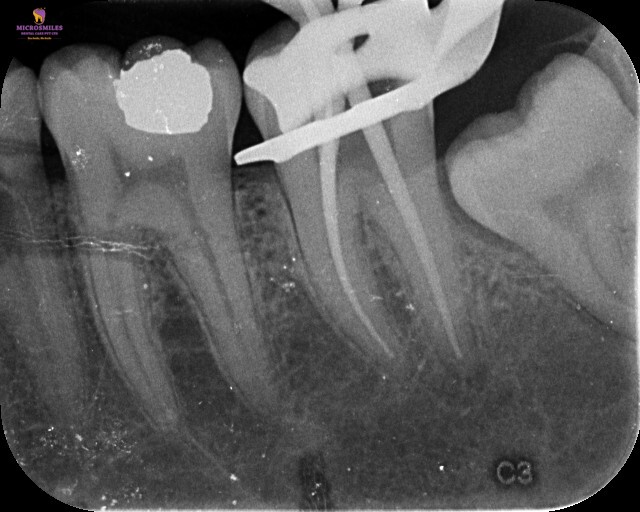

At Microsmiles, every root canal is performed under a high-resolution dental microscope, allowing our specialists to treat even the most complex canals with pinpoint accuracy. This level of detail isn’t just high-tech-it leads to faster treatment, fewer appointments, and long-lasting results.

Our microscope-enhanced approach ensures we do things right the first time-minimizing the need for return visits or repeat procedures. That means you spend less time in the dental chair, and more time doing what you love.